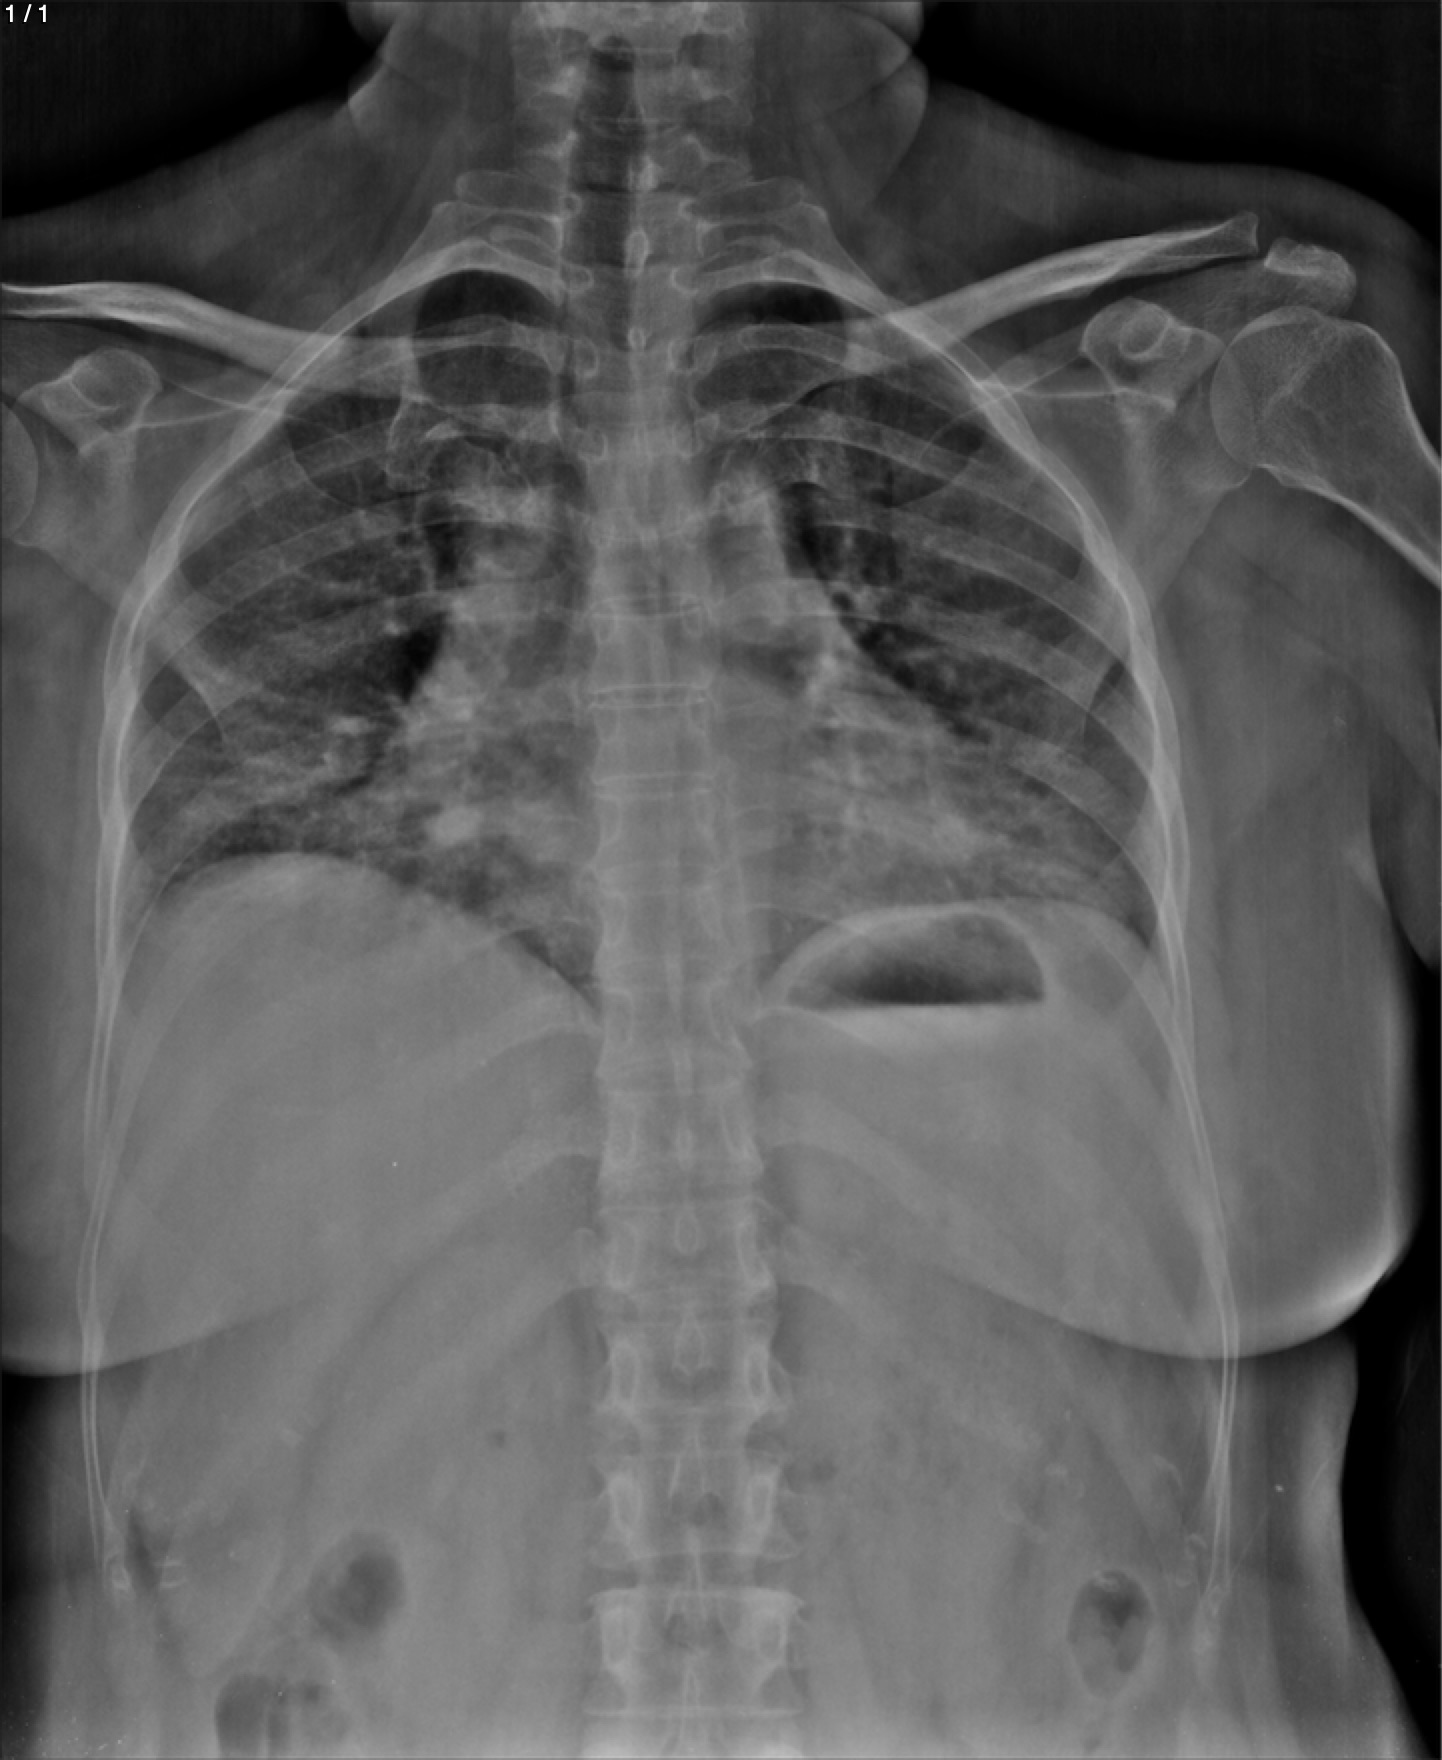

Maria Esther Garcia Najera - Unnamed